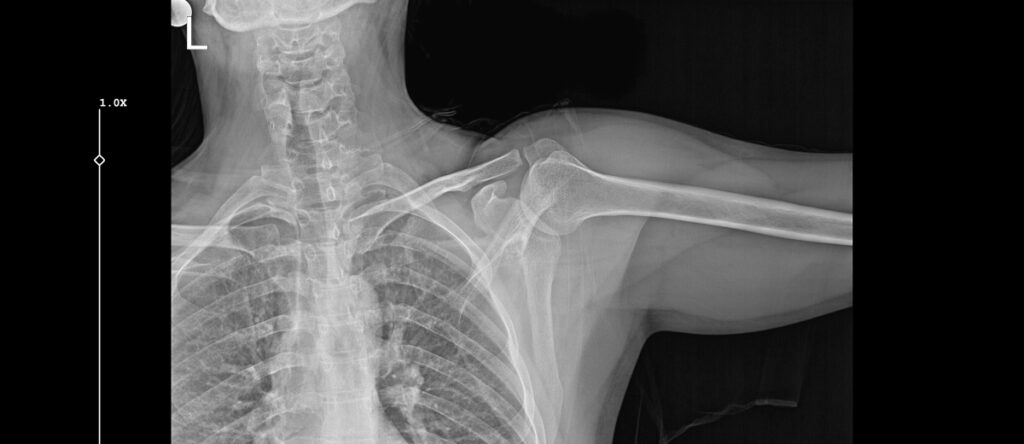

L’ecografia della spalla è un esame diagnostico non invasivo che utilizza ultrasuoni per visualizzare i tessuti molli dell’articolazione scapolo-omerale. A differenza della radiografia, che mostra principalmente le ossa, l’ecografia permette di studiare muscoli, tendini, legamenti e borse sierose, strutture fondamentali per il movimento e la stabilità della spalla. Si tratta di un’indagine particolarmente utile per valutare la cuffia dei rotatori, il gruppo di quattro tendini (sovraspinato, sottospinato, piccolo rotondo e sottoscapolare) più frequentemente coinvolto in lesioni e infiammazioni.

L’ecografia della spalla permette di visualizzare numerose strutture e alterazioni patologiche. In particolare, l’esame consente di identificare:

- lesioni parziali o complete dei tendini della cuffia dei rotatori

- tendiniti e tendinosi, ovvero processi infiammatori o degenerativi a carico dei tendini

- calcificazioni tendinee, depositi di sali di calcio che possono causare dolore intenso

- borsiti, infiammazioni delle borse sierose che facilitano lo scorrimento dei tendini

- versamenti articolari o raccolte di liquido

- rotture muscolari ed ematomi conseguenti a traumi

- ispessimenti o alterazioni strutturali della capsula articolare.

Il medico può inoltre valutare il tendine del capo lungo del bicipite, frequentemente coinvolto in patologie della spalla, e osservare il movimento delle strutture durante specifici gesti articolari. Questa caratteristica dinamica dell’ecografia rappresenta un vantaggio rispetto ad altre metodiche di imaging statico.